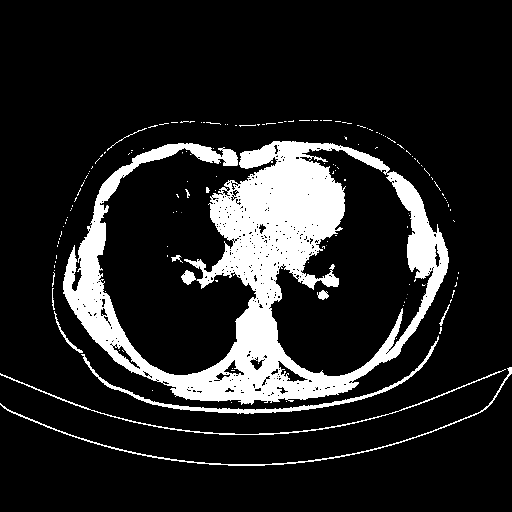

Generated VENOUS CT scan (A→B translation)

Full window (WL 1023.5, WW 4095 β†’ Low βˆ’1024, High +3071)

Actual HU range: [-1024.0, 3071.0]